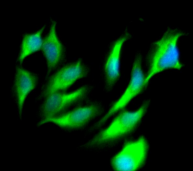

Immunofluorescent analysis of Hela cells using CSB-MA0157131A0m at a dilution of 1:100 and Alexa Fluor 488-congugated AffiniPure Goat Anti-Mouse IgG(H+L)

Immunofluorescent analysis of PC-3 cells using CSB-MA0157131A0m at a dilution of 1:100 and Alexa Fluor 488-congugated AffiniPure Goat Anti-Mouse IgG(H+L)

Immunofluorescent analysis of U251 cells using CSB-MA0157131A0m at a dilution of 1:100 and Alexa Fluor 488-congugated AffiniPure Goat Anti-Mouse IgG(H+L)